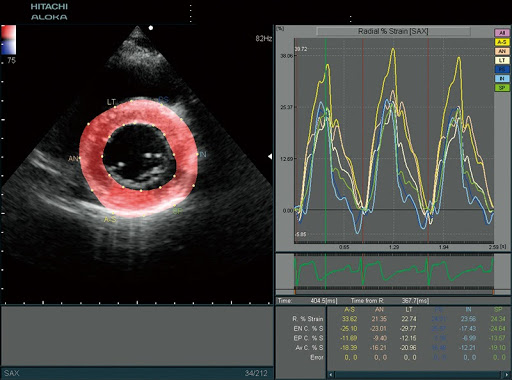

Расширенные возможности визуализации:

- Цветной и тканевой М-режим